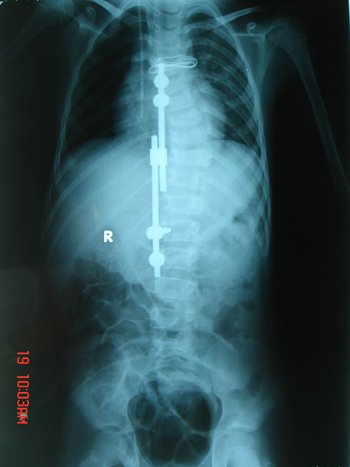

12岁男孩脊柱扭成麻花 专家手术男孩挺直腰杆

脊柱侧弯引起驼背弯腰 手术宜早不宜迟

小伙受脊柱重度畸形困扰多年 驼背矫正手术 造